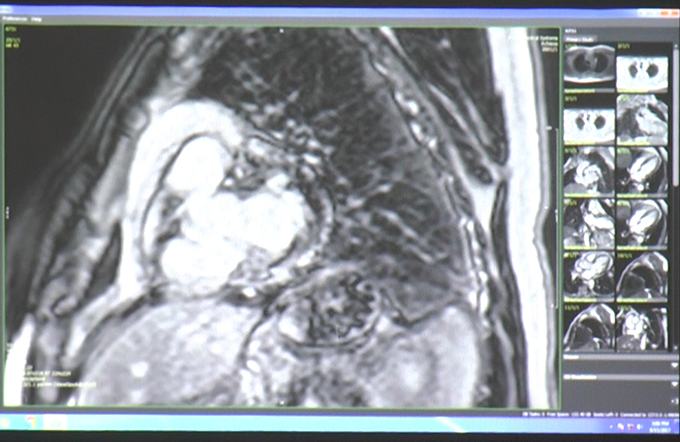

Case Discussion: Non- Ischemic Cardiomyopathies Part I

IACI 2017